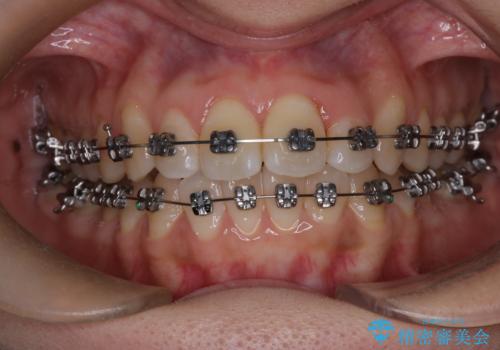

- メタル装置

- 前歯のがたつきを治したいという主訴で来院されました。1年後に転勤の可能性があり短期間での治療を希望されました。今回は非抜歯の治療を計画し、IPRと拡大をし、前歯の叢生を改善しました。

前歯のがたつきを治しながら2番の反対咬合も改善させました。短期間で終了し満足していただけました。